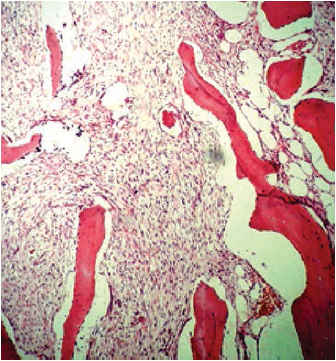

El procedimiento se realizó el 30 de marzo de 2016. El espécimen extraído se envió al Departamento de Patología del HUSI, que confirmó el diagnóstico histopatológico previo al procedimiento, de osteosarcoma fibroblástico de bajo grado, donde se evidenciaba un patrón celular fusiforme y fibroblástico, con matriz osteoide (figuras 4, 5, 6, 7). En este caso, el Departamento de Patología consideró que los estudios de inmunohistoquímica no eran necesarios.

Los subgrupos histológicos convencionales incluyen un patrón osteoblástico, condroblástico y fibroblástico, definido de acuerdo con la abundancia y naturaleza de la matriz producida por las células tumorales. El más común aparece en la mandíbula, el patrón condroblástico, cercano a un 50 % de todos los casos [3,4,5,6].